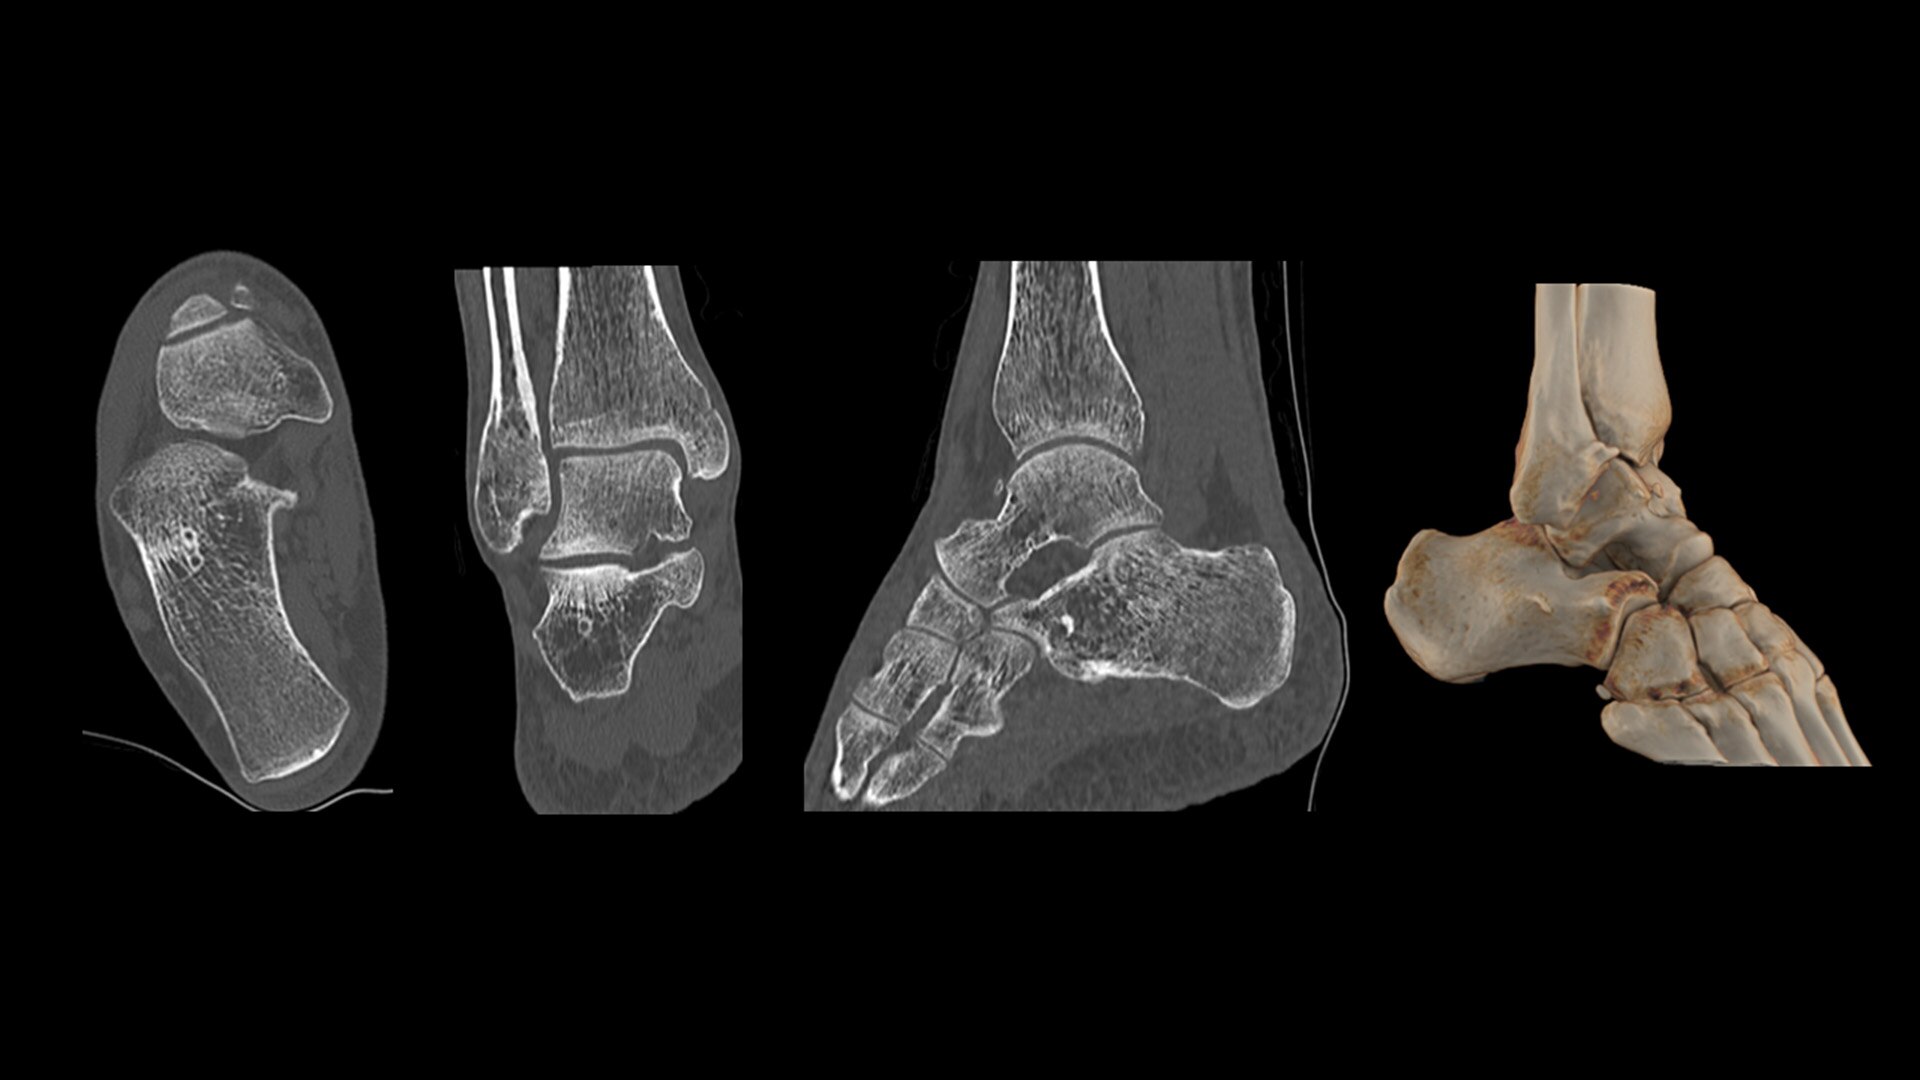

Cardiac CT has become a front-line, non-invasive imaging tool for diagnosing, treatment planning and monitoring of cardiovascular disease

Healthcare providers are striving to improve patient health but are struggling with increasingly complex exams, insufficient or inexperienced staff, and operational and capital efficiency. Revolution™ Vibe, designed to deliver leading-edge technology, features advanced cardiovascular capability. It improves patient access and operational efficiency, prioritizes patient care and supports your facility's growth with lower lifecycle costs.

Consistent, exceptional image quality for every patient

Unlimited 1-Beat Cardiac is designed to provide consistent, high-quality imaging for accurate diagnoses, even in challenging patients with atrial fibrillation, breath-holding difficulties, heavily calcified coronaries, in-stent restenosis, and situations where an ECG trace is unavailable.